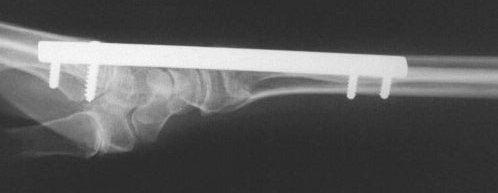

Clinical Example: Distraction plate fixation distal radius fracture

distal radius fracture